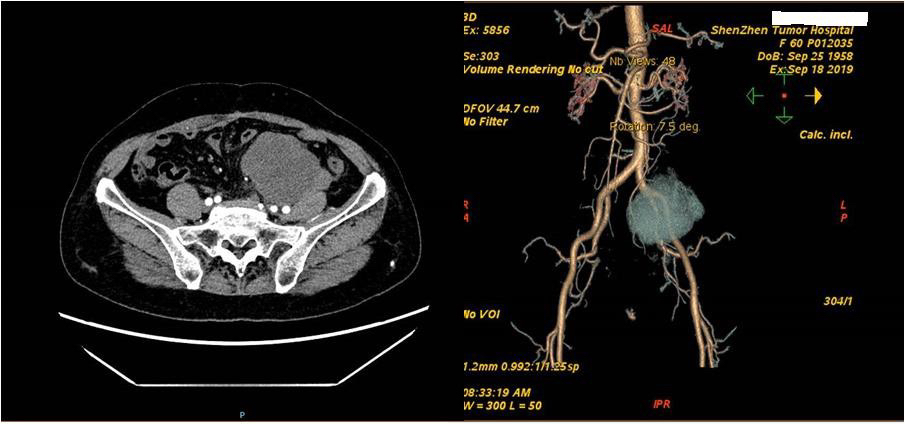

术前影像学资料

入我院后, 给予完善腹部CT等术前检查,考虑腹膜后-左侧髂窝见不规则分叶状肿块,约8.4×6.7× 7.9cm,包饶左侧卵巢静脉,肿块紧贴左侧髂总动脉、髂内、髂外动脉近端及左侧腰大肌, 左侧输尿管中段受压移位,致左肾轻度积液,考虑肿瘤复发。术前王天宝教授团队经过详细 评估后,考虑肿瘤与左侧输尿管关系密切,请泌尿外科会诊先行左侧输尿管双J管植入术。 完善术前准备后,遂于2019.09.19日全麻行腹膜后复发脂肪肉瘤切除术+部分乙状结肠切除 术+肠粘连松解术+左侧输尿管双J管置入术。术中:见肠粘连严重,小心仔细分离腹腔粘连 后,可见一大小约8*8*7cm肿物,质地硬,活动度差,与乙状结肠及其系膜融合,与左侧输 尿管紧密粘连,遂钝锐性结合逐步分离肿物,并切除部分乙状结肠及其系膜。手术用时3小 时,术中出血约500ml,术后病人安返病房。术后第2日查房,患者生命体征平稳,于床旁坐 起,无明显不适。